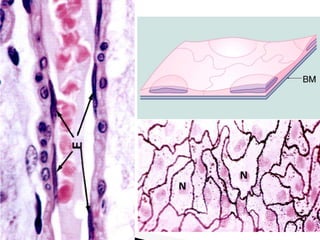

Células caliciformes, se observa la mucina en color magenta, histoquímica PAS.

Epitelio cilíndrico simple mucosecretor de la mucosa gástrica, se observa la mucina en

color magenta, histoquímica PAS y van Gieson.

Glándulas mucosas de Littré en la uretra femenina, H y E.